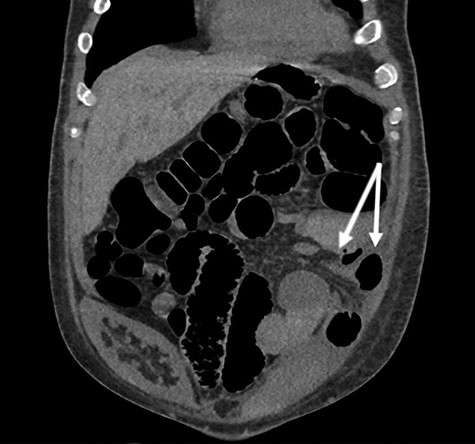

Eventually, the patient had a return of bowel function and his diet was advanced. His renal function also improved. The patient was discharged home in stable condition on POD 15 with close follow-up arranged in the outpatient transplant clinic. However, the patient was then readmitted 2 days after his discharge due to abdominal pain and inability to tolerate oral intake. He was managed conservatively, and TPN was again initiated. He underwent CT imaging, which demonstrated a partial small bowel obstruction with a transition point in the left lower quadrant of the abdomen (Fig. 1). He was operatively explored and found to have a loop of small bowel herniated into the left retroperitoneal space through a peritoneal defect. A small bowel resection with staple-assisted side-to-side enteroenterostomy was performed, and the hernia defect was closed primarily. He progressed well postoperatively and was discharged home in stable condition on POD 7.

Coronal view of non-contrast CT with arrows denoting herniated mesentery and small bowel into the retroperitoneum. Note the nonfunctional prior renal transplant in the right hemipelvis.